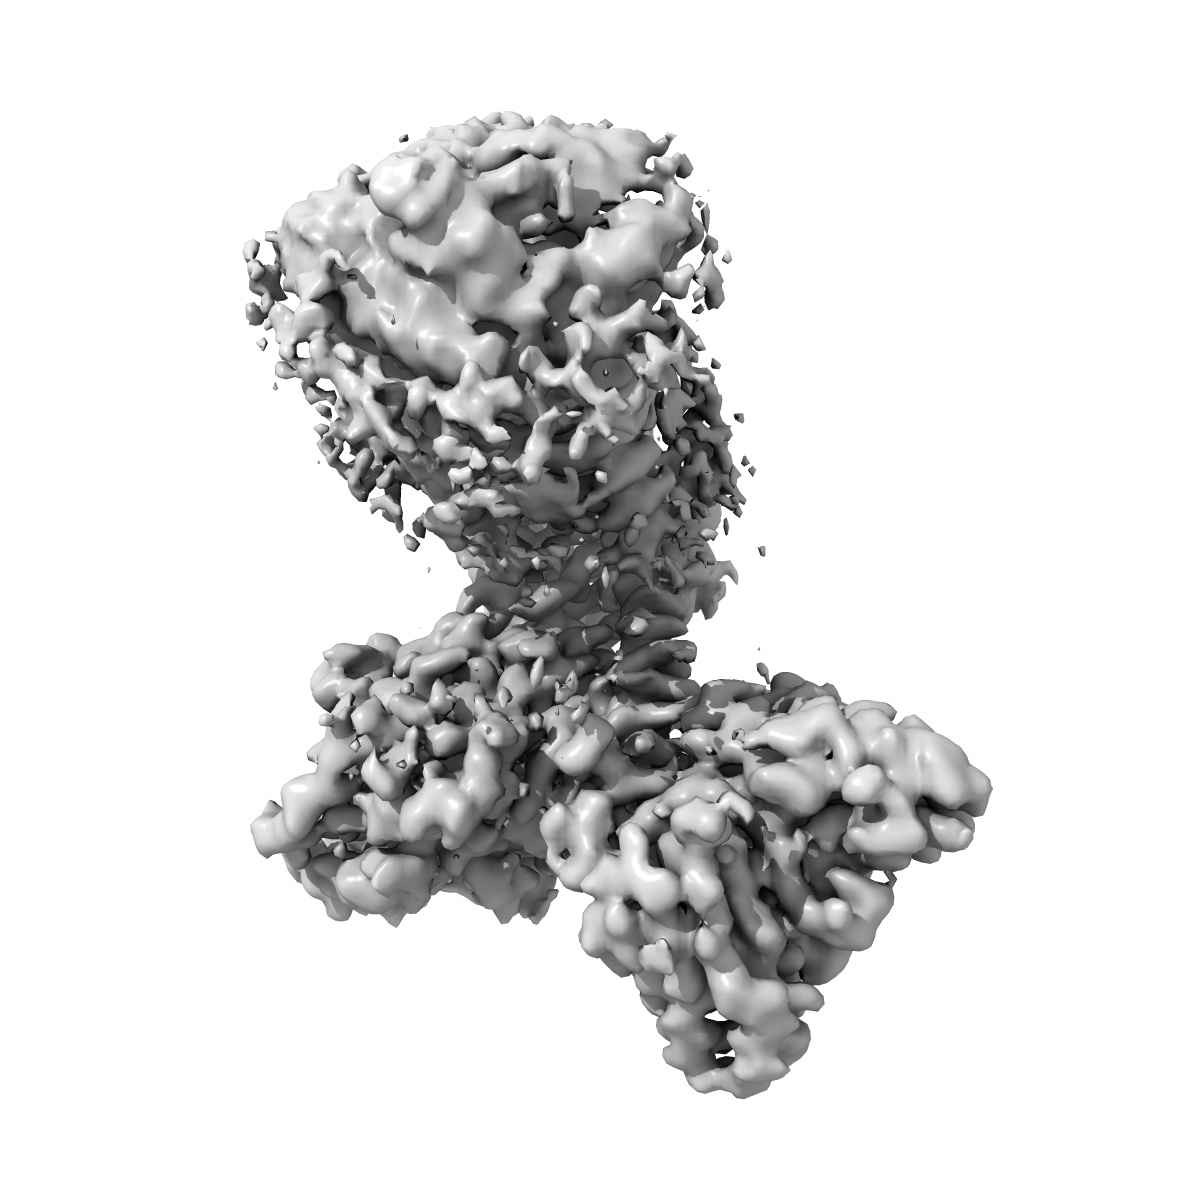

Cryo-EM structure of the TUG891 bound GPR120-Giq complex (consensus map)

Single-particle2.64 Å

Sample: Cryo-EM structure of the TUG891 bound GPR120-Giq complex

Unsaturated bond recognition leads to biased signal in a fatty acid receptor.

(2023) Science , 380 , eadd6220 - eadd6220